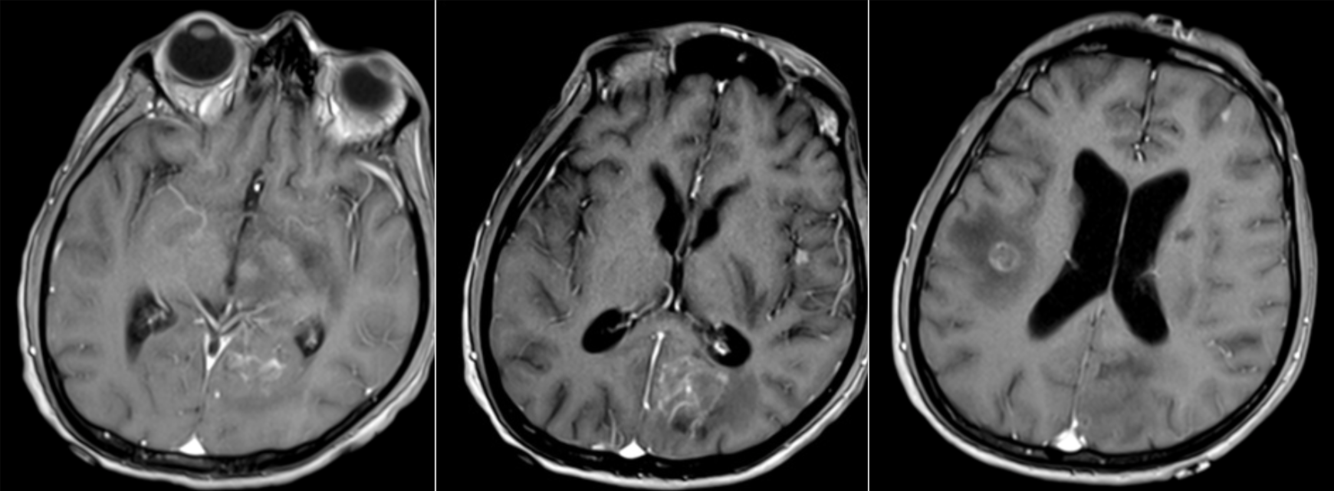

A 56 year-old immunocompromised man presented with seizures.

Aspergillosis

Imaging